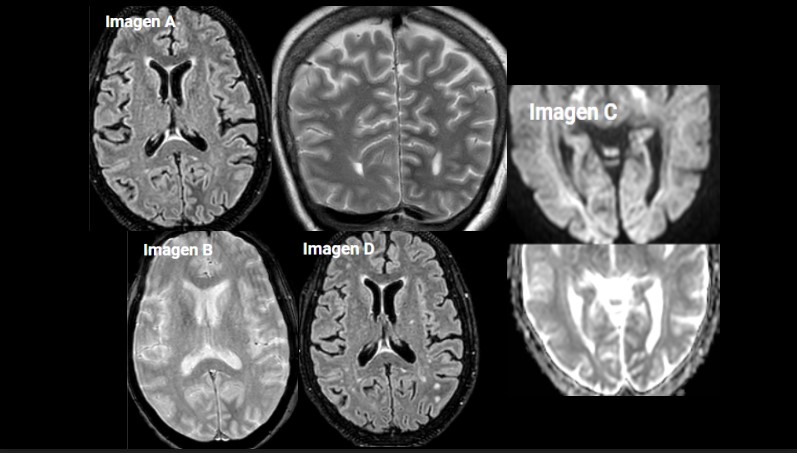

Imagen A. RM craneal secuencia FLAIR axial y T2 coronal. Hipointensidad subcortical difusa, de bordes mal definidos, en la sustancia blanca del lóbulo occipital izquierdo y ligera hiperintensidad cortical.

Imagen B. RM craneal secuencia T2* EG. Hipointensidad de la sustancia blanca del lóbulo occipital izquierdo, sin mostrar artefactos por susceptibilidad magnética, sin restos de hemosiderina.

Imagen C. RM craneal secuencia difusión (factor b= 2500 s/mm²) y mapa ADC, muestra una sutil restricción asociada.

Imagen D. RM craneal secuencia FLAIR axial. Realizada 6 semanas después tras resolución de la hiperglucemia, observando desaparición de los hallazgos visualizados en el estudio previo.

En las RM se identifica una hipointensidad en T2 y FLAIR en la sustancia blanca subcortical del lóbulo occipital afecto, junto con ligera hiperintensidad de la cortical adyacente. En una secuencia T2 eco-gradiente también aparece una hipointensidad de la sustancia blanca. En la difusión se puede objetivar una ligera hiperintensidad de la cortical adyacente. Tras la administración de contraste, se observa un realce leptomeníngeo en región parieto-occipital.